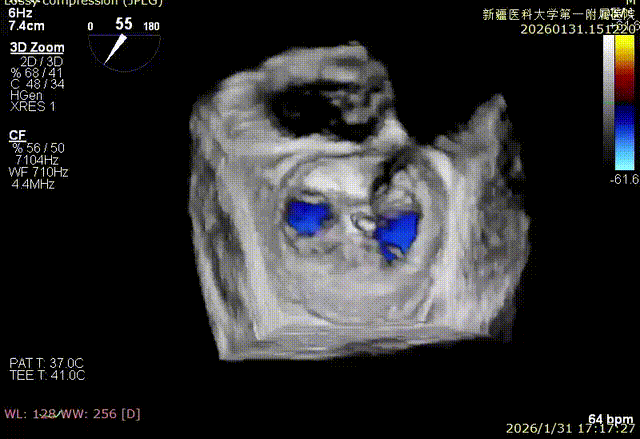

3D enface反流充分降低